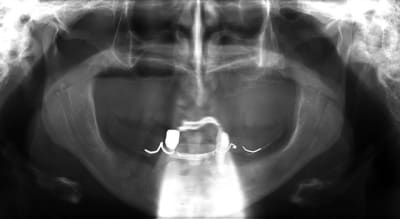

j'ai besoin de 4 implants au maxillaire pour faire tenir son complet.

dans la zone postérieur, pas de problème, mais devant, c'est une autre histoire.

si tu as un pano ça permet de situer differement

un pano stp D57.

voili, voila...

avant de faire la tomosynthèse je comprenais pas pourquoi j'avais aussi peu de contraste.

le patient ne souhaite pas, ou ne peut pas se faire poser 6 implants en haut, donc...overdenture sur 4. (si possible)

Cas pour xpav e1rypn - Eugenol